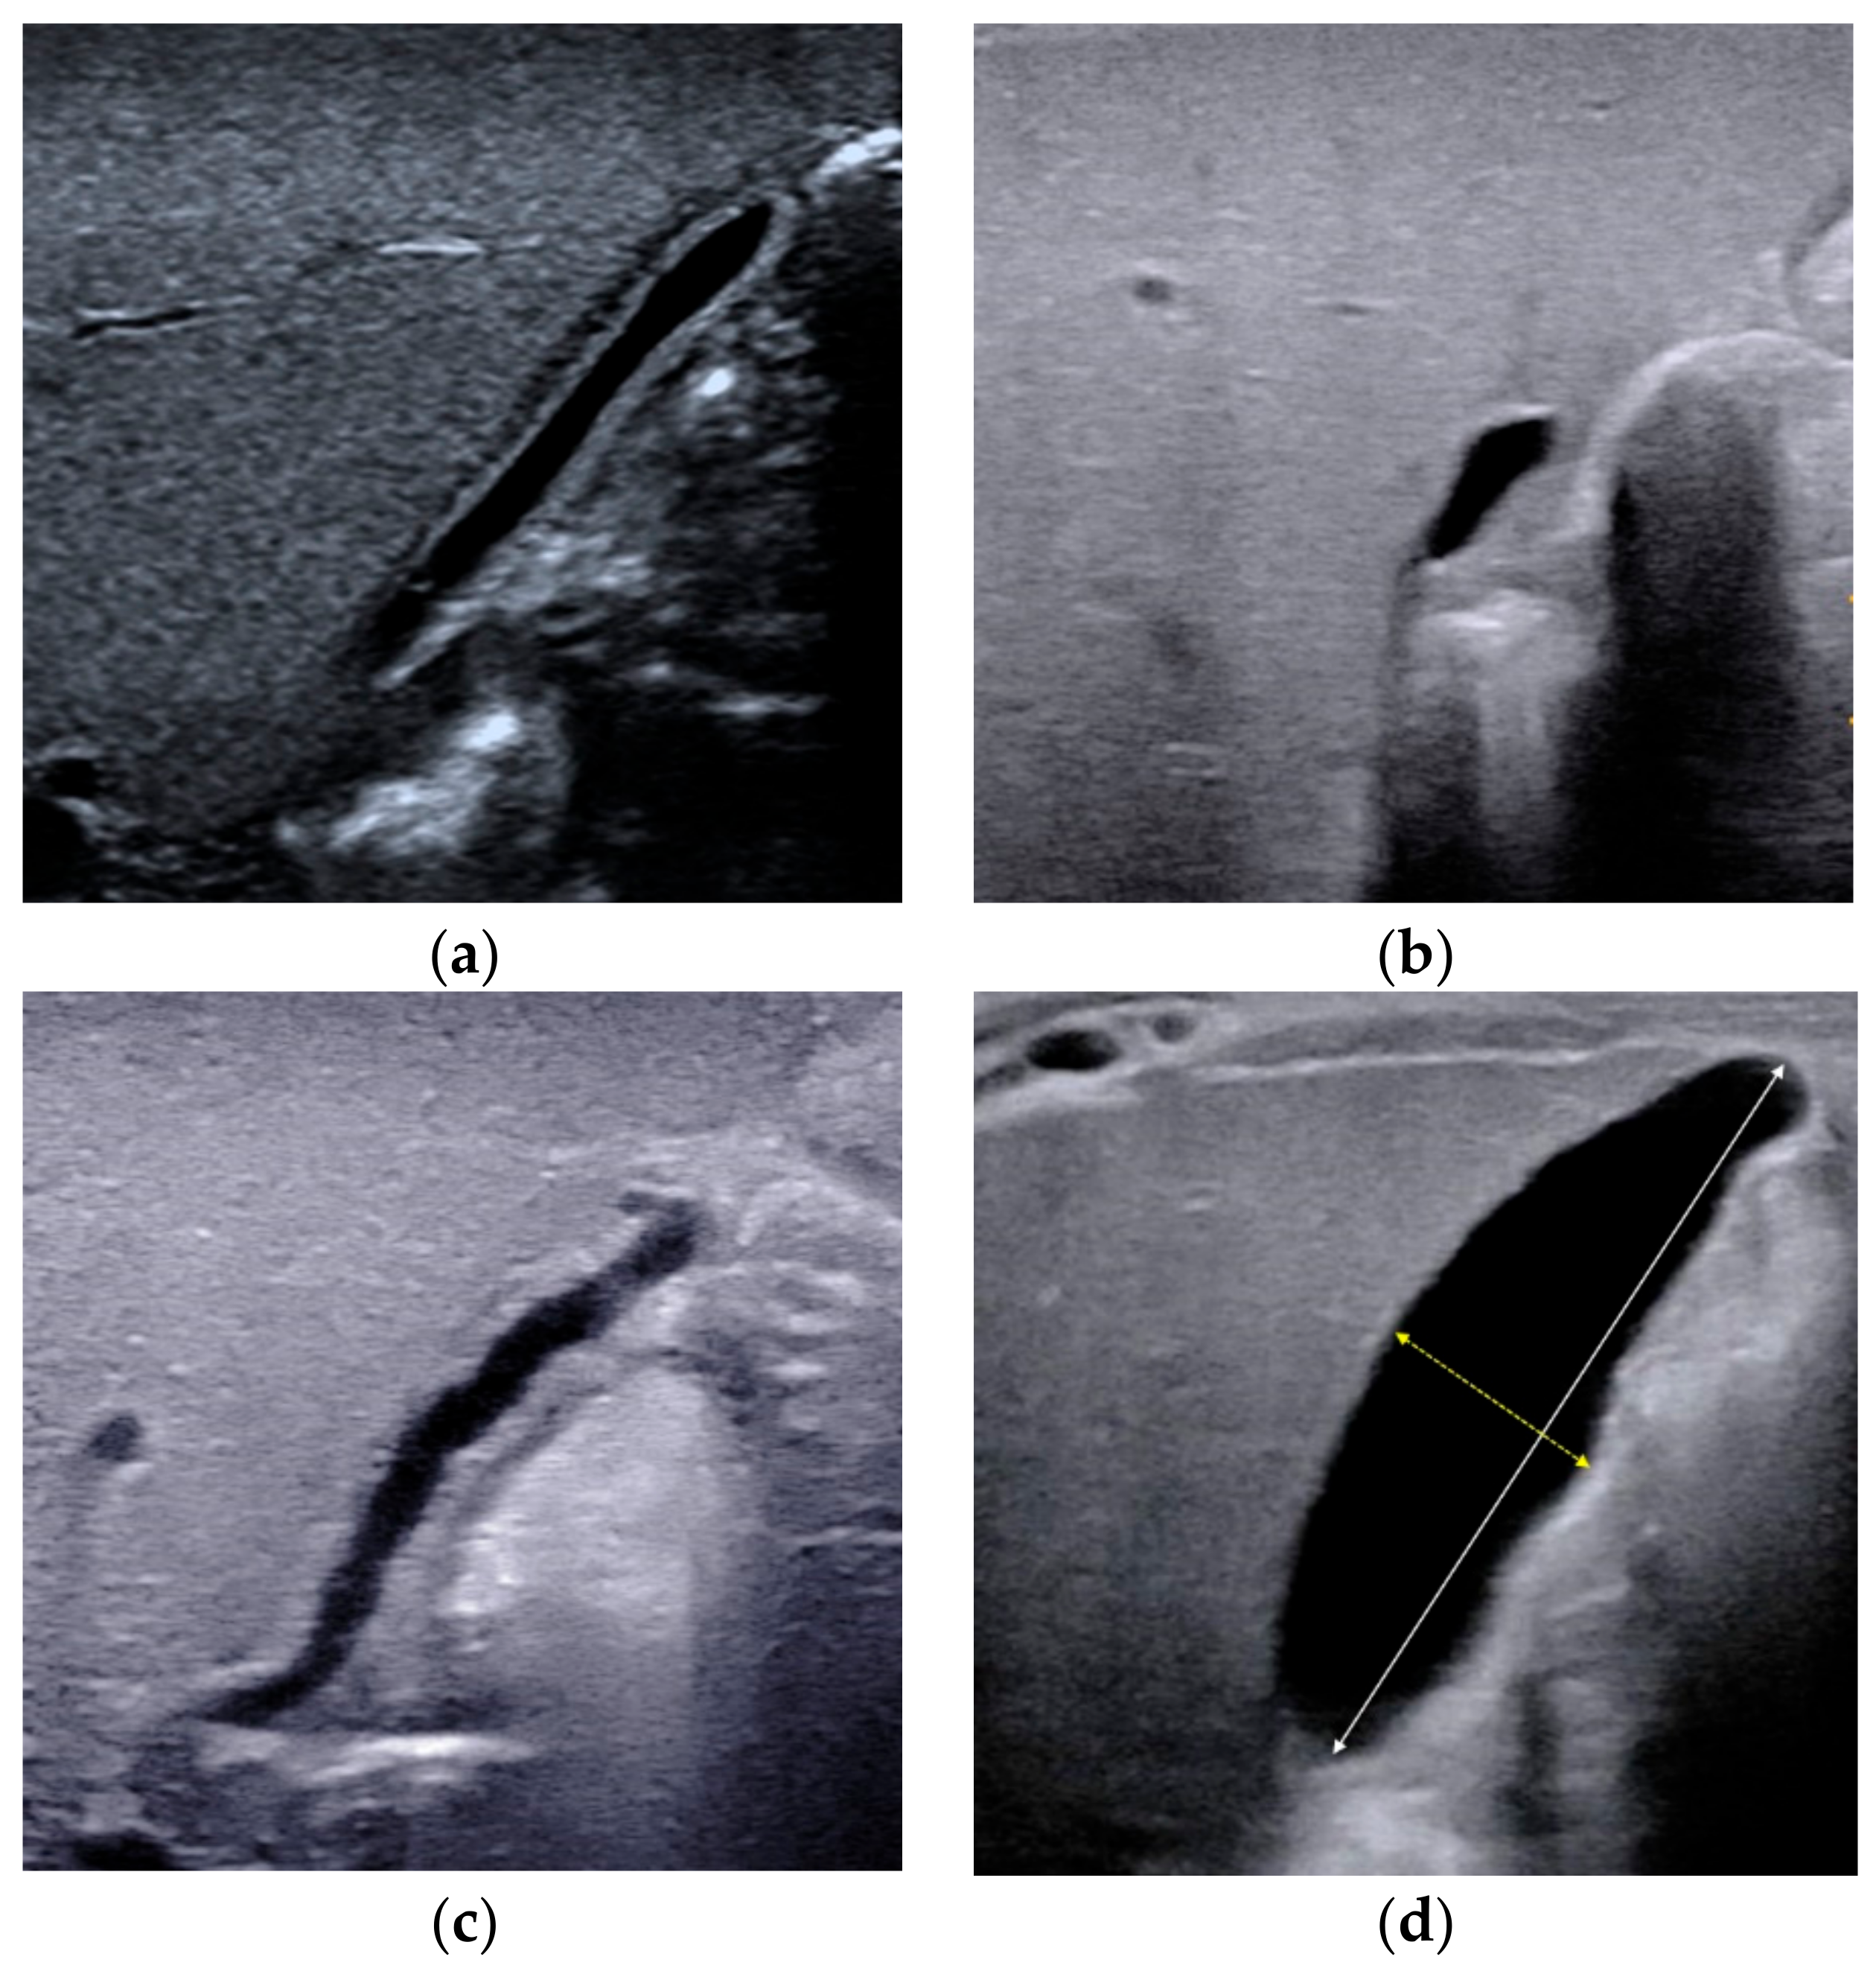

2.2. Triangular Cord Sign

2.3. Porta Hepatis Macro- or Microcyst

2.4. Enlarged Hepatic Hilar Lymph Node (LN)

2.5. Other Helpful US Features

- Choi, S.-O.; Park, W.-H.; Lee, H.-J.; Woo, S.-K. ‘Triangular cord’: A sonographic finding applicable in the diagnosis of biliary atresia. J. Pediatr. Surg. 1996, 31, 363–366. [Google Scholar] [CrossRef]

- Park, W.-H.; Choi, S.-O.; Lee, H.-J.; Kim, S.-P.; Zeon, S.-K.; Lee, S.-L. A new diagnostic approach to biliary atresia with emphasis on the ultrasonographic triangular cord sign: Comparison of ultrasonography, hepatobiliary scintigraphy, and liver needle biopsy in the evaluation of infantile cholestasis. J. Pediatr. Surg. 1997, 32, 1555–1559. [Google Scholar] [CrossRef]

- Mittal, V.; Saxena, A.K.; Sodhi, K.S.; Thapa, B.R.; Rao, K.L.N.; Das, A.; Khandelwal, N. Role of Abdominal Sonography in the Preoperative Diagnosis of Extrahepatic Biliary Atresia in Infants Younger Than 90 Days. AJR Am. J. Roentgenol. 2011, 196, W438–W445. [Google Scholar] [CrossRef]

- Kotb, M.A.; Kotb, A.; Sheba, M.F.; Koofy, N.M.E.; El-Karaksy, H.M.; Abdel-Kahlik, M.K.; Abdalla, A.; El-Regal, M.E.; Warda, R.; Mostafa, H.; et al. Evaluation of the Triangular Cord Sign in the Diagnosis of Biliary Atresia. Pediatrics 2001, 108, 416–420. [Google Scholar] [CrossRef]

- Koob, M.; Pariente, D.; Habes, D.; Ducot, B.; Adamsbaum, C.; Franchi-Abella, S. The porta hepatis microcyst: An additional sonographic sign for the diagnosis of biliary atresia. Eur. Radiol. 2017, 27, 1812–1821. [Google Scholar] [CrossRef]

- Caponcelli, E.; Knisely, A.S.; Davenport, M. Cystic biliary atresia: An etiologic and prognostic subgroup. J. Pediatr. Surg. 2008, 43, 1619–1624. [Google Scholar] [CrossRef]

- Shan, Q.-Y.; Liu, B.-X.; Zhong, Z.-H.; Chen, H.-D.; Guo, Y.; Xie, X.-Y.; Zhou, W.-Y.; Jiang, H.; Zhou, L.-Y. The Prognosis of Type III Biliary Atresia with Hilar Cyst. Indian J. Pediatr. 2021, 88, 650–655. [Google Scholar] [CrossRef]

- Kim, W.S.; Cheon, J.-E.; Youn, B.J.; Yoo, S.-Y.; Kim, W.Y.; Kim, I.-O.; Yeon, K.M.; Seo, J.K.; Park, K.-W. Hepatic Arterial Diameter Measured with US: Adjunct for US Diagnosis of Biliary Atresia. Radiology 2007, 245, 549–555. [Google Scholar] [CrossRef]

| Triangular cord sign | The thickness of the echogenic anterior wall of the right portal vein, with or without HA. | >2.0 mm not including HA, or >4.0 mm including HA | ≤2.0 mm not including HA, or ≤4.0 mm including HA | Strongly suggest BA |

| Porta hepatis macro- or microcyst | The cyst in front of the right portal vein at the hepatic portal. | Presence | Absence | Strongly suggest BA |